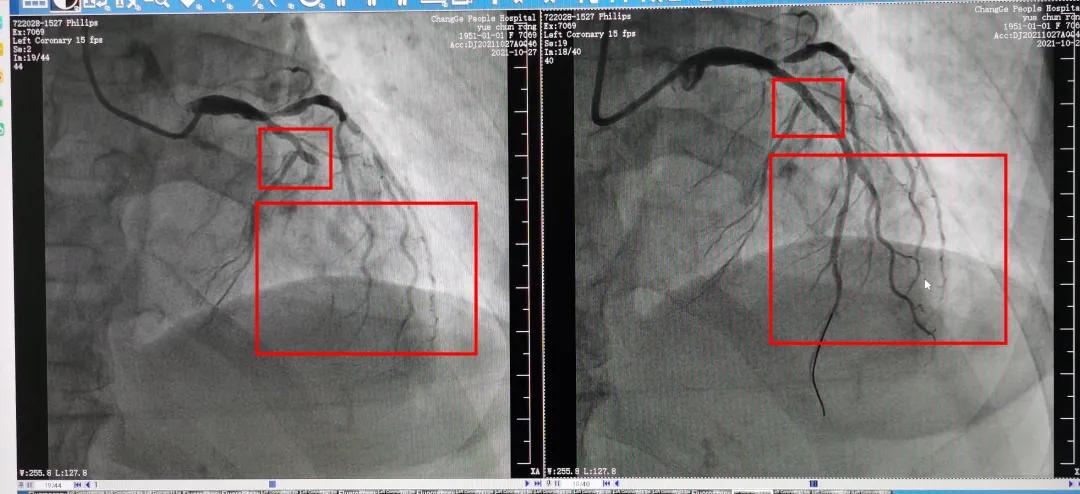

图为岳女士手术前后的血管造影图,可以非常明显看出手术前后的血液流动情况。